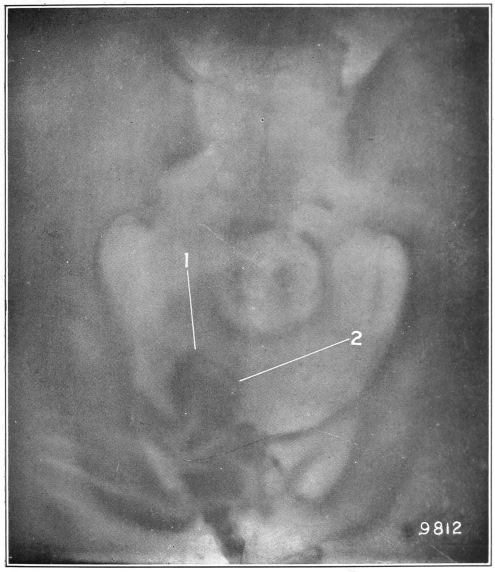

Fig. 4.

1, The dotted lines indicate the normal direction of the anus and rectum; 2, 4, the cavities or pouch formed by dilatation or ballooning from the storage of impacted feces; 3, a probe bent at right angles, and introduced through a speculum, to ascertain the depth of the pouch, which is frequently found to be two and a half inches.